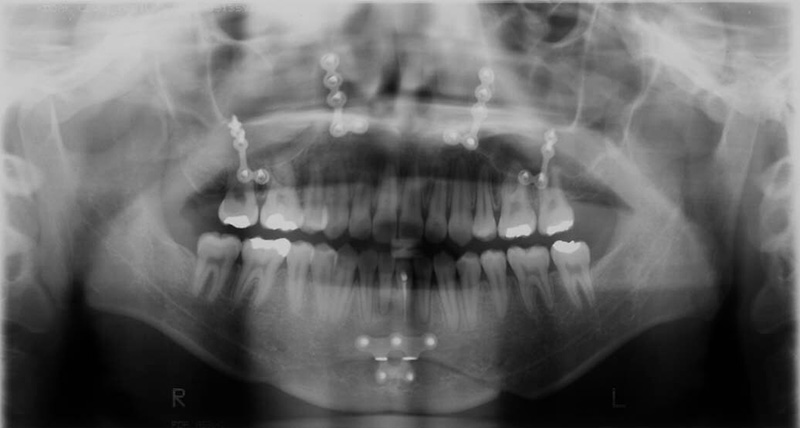

| パノラマ所見 | 下顎左側中切歯に根管治療の既往が認められた。 |

| リスク | 外科手術中に起きた下顎左側中切歯の骨性癒着による歯牙と咬合への影響が懸念される。 |